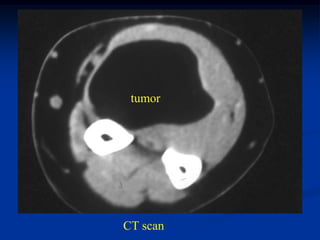

Case #1190

66 year female with intramuscular lipoma forearm

tumor

CT scan